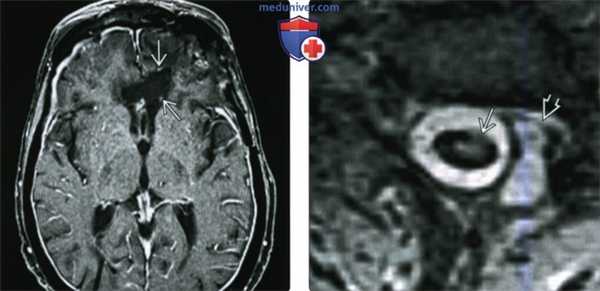

(Слева) При аксиальной МРТ Т2 ВИ у пациента, у которою несколько месяцев назад был удален метастаз меланомы из лобной доли, визуализируется постоперационная полость. Борозды и Сильвиевы щели очерчены неявным гипоинтенсивным «ободком» (поверхностный сидероз).

(Справа) При аксиальной MPT Т2*GRE у этою же пациента определяется более выраженный сидероз с поражением Сильвиевых щелей и борозд. На GRE Т2* отложения гемосидерина становятся более очевидными из-за блюминга.

(Слева) При аксиальной МРТ Т1 ВИ С+ FS у этого же пациента определяются очаговое накопление контраста в постоперационной полости. Видны также очаги грануляционной ткани вдоль края зоны вмешательства, которые, скорее всего, обусловлены продолжающимся кровоизлияниями, приводящими к поверхностному сидерозу.

(Справа) При аксиальной МРТ Т2 ВИ у пациента с травмой шеи определяется прерывание гипоинтенсивного «ободка» гемосидерина вследствие отсутствия мягкой оболочки спинного мозга в зоне отрыва корешка. Обратите внимание на псевдоменингоцеле (N. Kumar, MD).